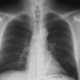

Metallic mercury thromboembolism